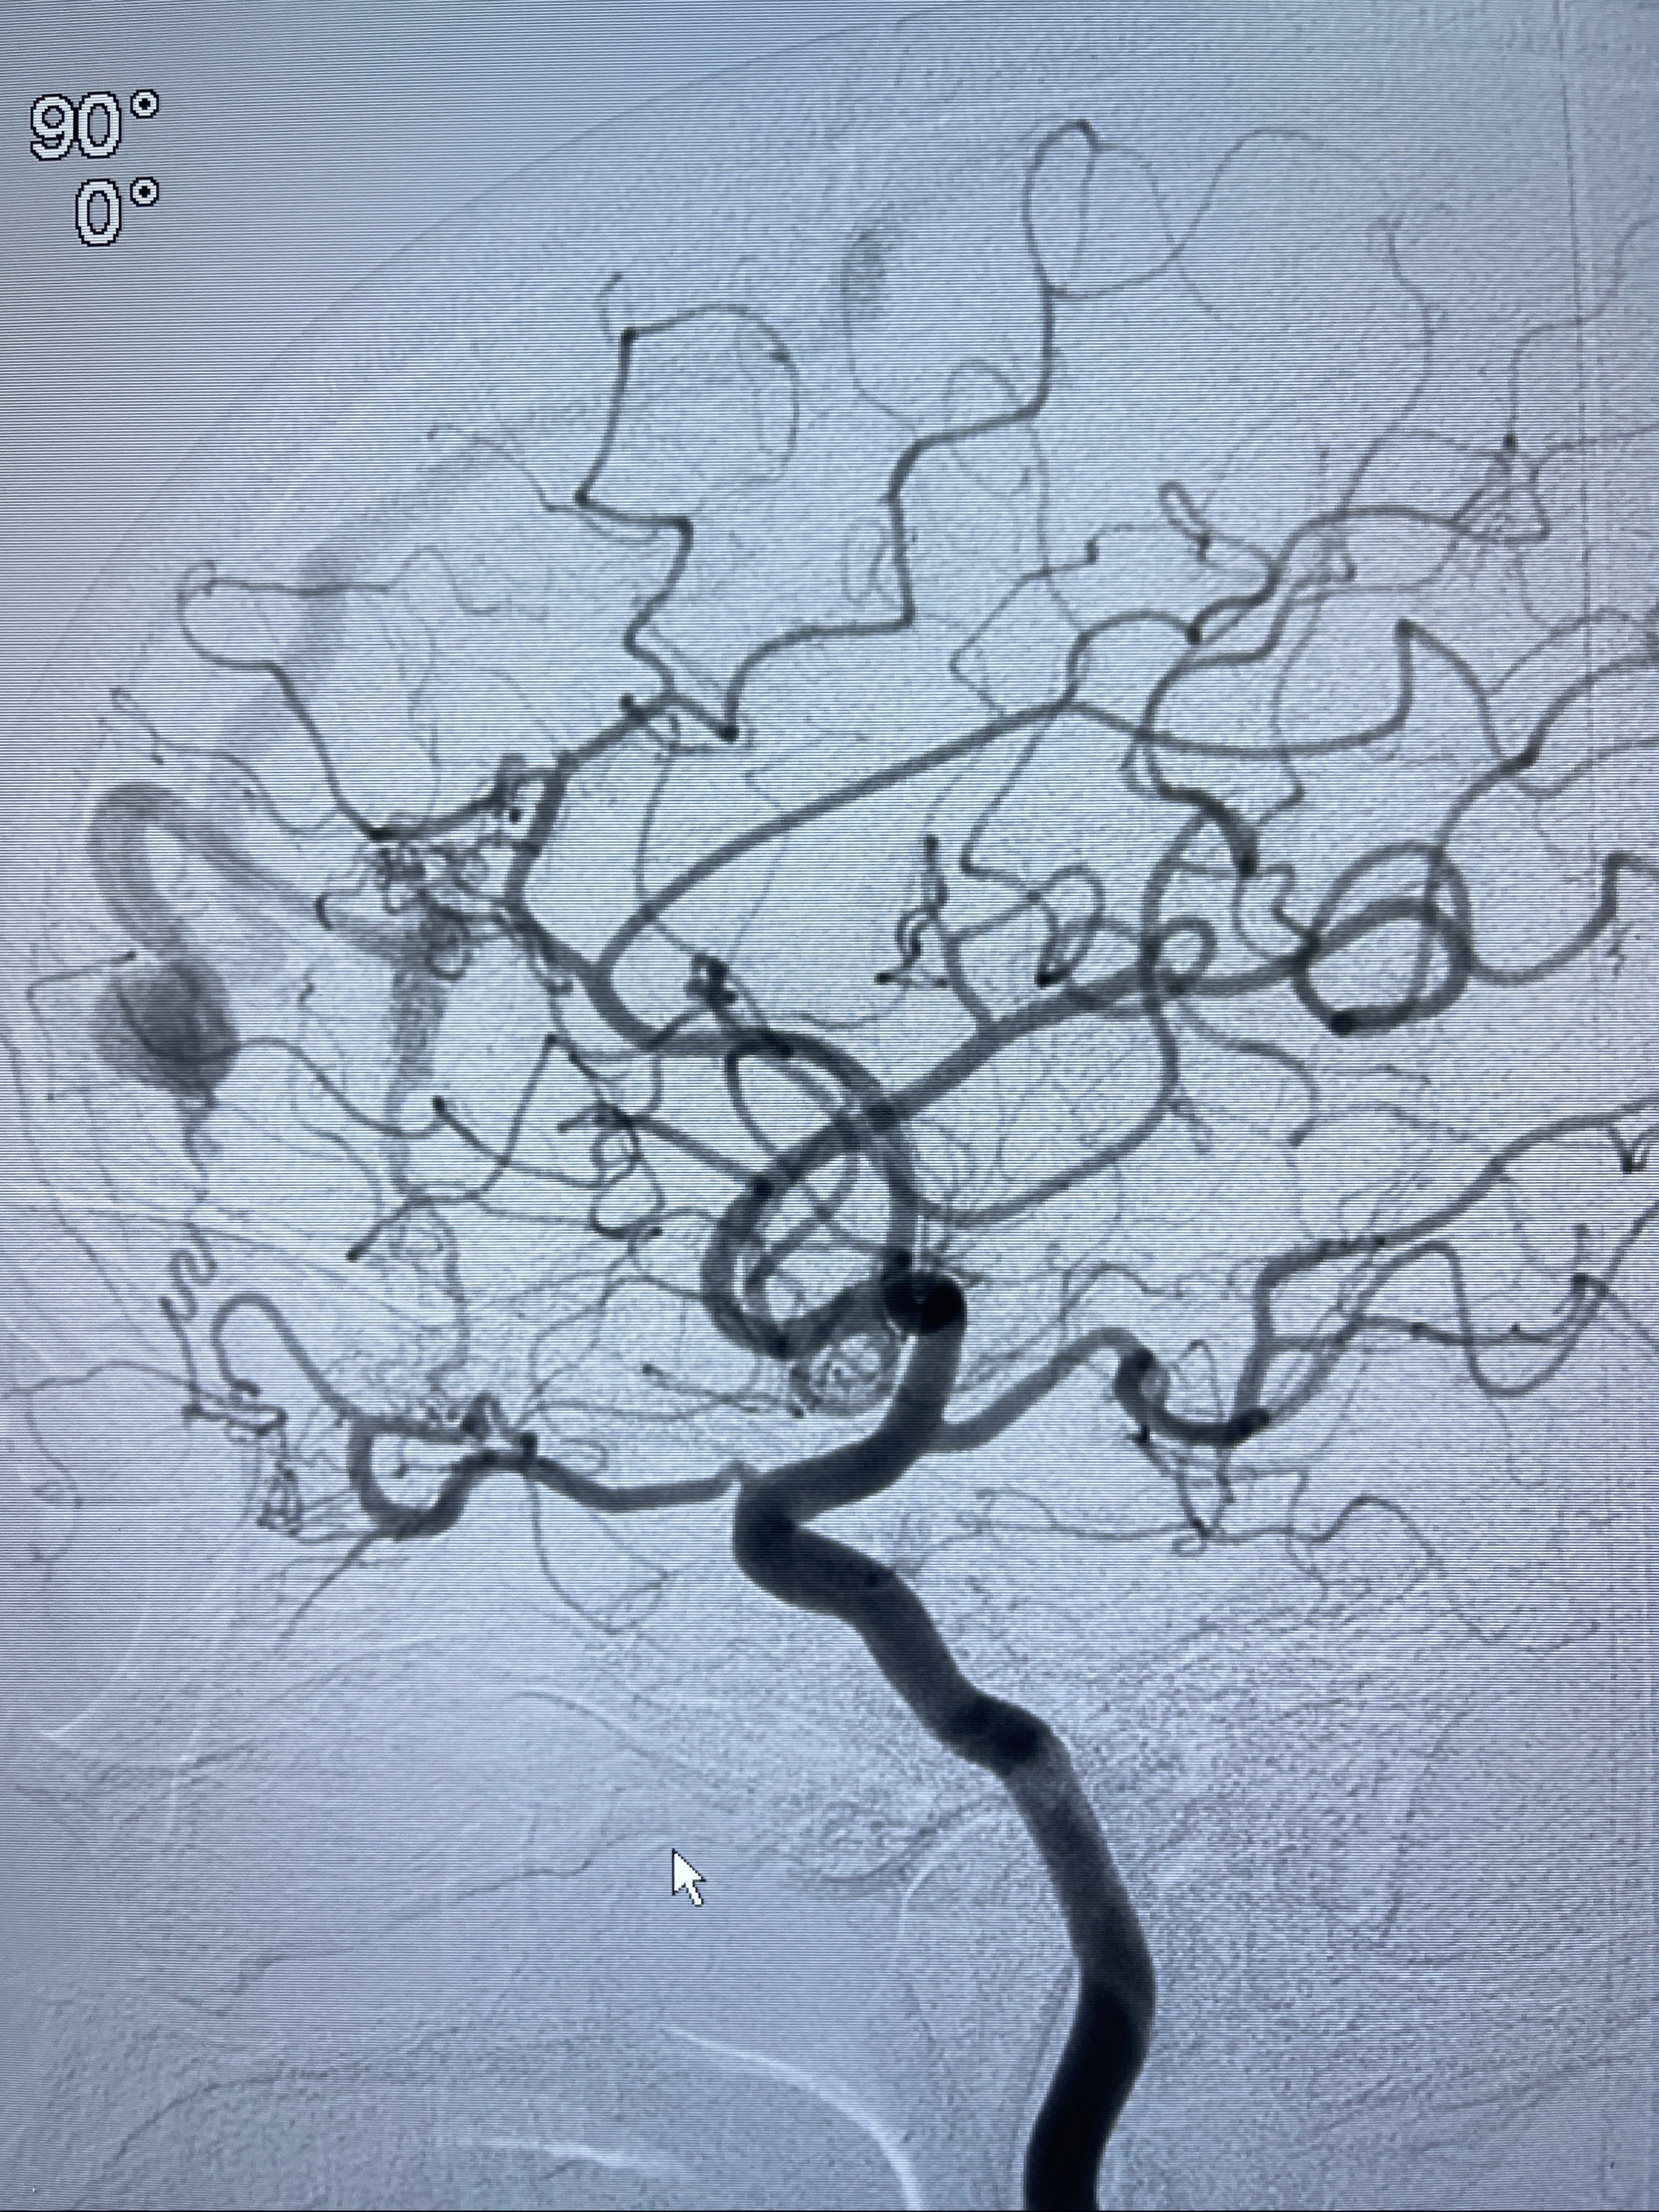

2023年8月21日]景德镇市第一人民医院脑血管造影检查,提示:主动脉弓、双侧颈总动脉、锁骨下动脉造影未见异常,左侧大脑前动脉静脉瘘。

2023-09-13全脑血管造影:前颅底硬脑膜动静脉瘘,供血动脉为双侧胼周动脉、眼动脉脑膜支,静脉向上矢状窦方向引流

治疗策略:

- 外科手术?

- 介入干预:静脉途径栓塞or动脉途径填塞?